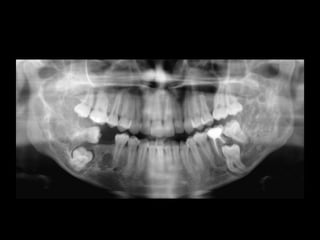

1. Radiographic evaluation, OPG shows multilocular

radiolucency with root resorption and

displacement of teeth

2. CT scan in case of larger lesions and esp maxillary

ameloblastoma